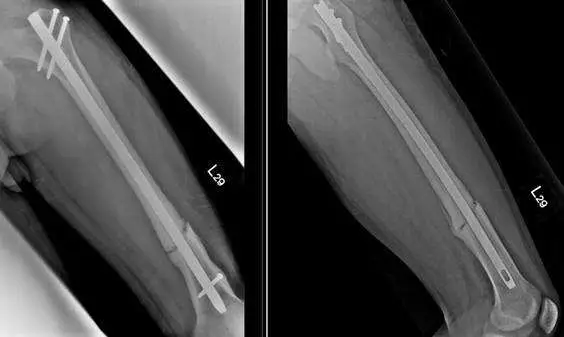

一位 32 歲男性左股骨幹骨折( femoral shaft fracture ),手術後 2年半,仍時常感到左大腿疼痛,無法負重行走,其 X光檢查結果如下圖。下列敘述何者錯誤?

X 光呈現正位(AP)及側位(lateral)兩個方向的股骨影像。可見股骨中段放置了一根骨髓內釘(intramedullary nail),釘體貫穿骨髓腔,近端與遠端均有鎖定螺釘(interlocking screws)固定。骨折部位可見大量骨痂(callus)形成,外觀蓬鬆豐厚、呈「象腳」(elephant's foot)外形,但骨折線仍清晰可辨,未見骨小樑跨越骨折端,代表雖有旺盛的生物癒合反應,骨折卻仍未癒合(nonunion)。此影像型態符合**增生性不癒合(hypertrophic nonunion)**的典型 X 光表現。骨髓內釘本身無明顯彎曲或斷裂,釘子較細,穩定性可能不足。

C此病例的診斷 為增生性不癒合( hypertrophic nonunion ),常因為骨折固定的穩定度不足而造成

D此病例可採用更換較大的骨髓 內釘( intramedullary nail )及骨移植( bone grafting )進行治療